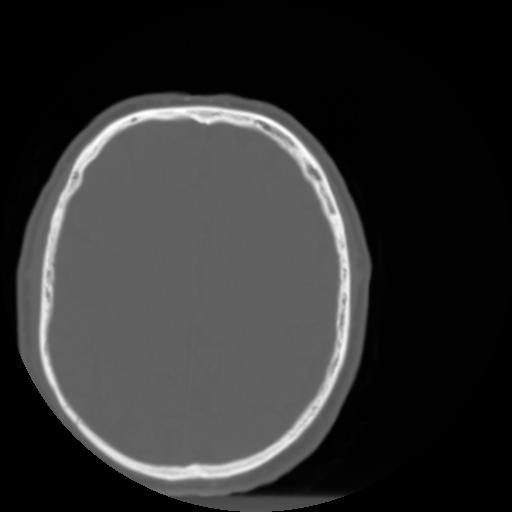

3 CEREBRO,,Axial,3.0,CEREBRO,,